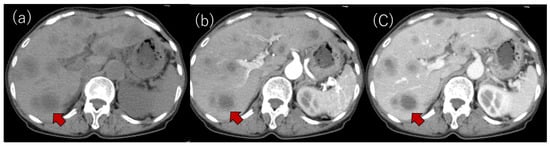

Laboratory examinations (Table 1) showed mild elevation of the serum aspartate aminotransferase and C-reactive protein (CRP) levels. The peripheral blood data, including the white blood cell count and platelet count, and the prothrombin time were found to be within the normal range. Tumor markers, such as carcinoembryonic antigen (CEA), carbohydrate antigen 19-9 (CA19-9), α-fetoprotein (AFP) and protein induced by vitamin K absence or antagonist-II (PIVKA-II), were within the normal ranges. Contrast-enhanced computed tomography (CE-CT) showed low-attenuation areas with mild peripheral enhancement at the arterial and portal phase (Figure 2), suggesting the development of metastatic liver tumors. However, no primary tumor candidate was found on the CE-CT. Esophagogastroduodenoscopy and colonoscopy did not reveal any malignant disease. In addition, despite the presence of suspected metastatic tumors on the US and CT, 18F-fluorodeoxyglucose positron emission tomography with CT (FDG-PET/CT) showed no significant uptake in the tumors (Figure 3).

Figure 3. (a) 18F-fluorodeoxyglucose positron emission tomography (FDG-PET) and (b) FDG-PET with CT. No apparently significant signal was observed in the tumors (arrowheads).

In the US findings (Aplio, Canon Medical Systems, Ohtawara, Tochigi, Japan), a hypoechoic tumor of 10 mm in size was observed (Figure 5a). On the Sonazoid contrast-enhanced US, the tumor showed very slight hypoenhancement in the arterial phase (Figure 5b), washout with peripheral enhancement in the portal phase (Figure 5c) and hypointensity in the Kupffer phase (Figure 5d). A percutaneous liver biopsy showed liver tissue with cell shedding, fibrotic changes, and infiltration of inflammatory cells, including lymphocytes and macrophages. There were no malignant findings. As a result, IPT was thus suggested (Figure 6). After two months of observation, the tumors spontaneously regressed and nearly vanished (Figure 7).

Figure 7. Changes in the US and CT findings: multiple tumors that had been suggested to be metastatic tumors (a,b) were barely detected after two months of observation; (a,b) US findings; (c,d) CT findings.